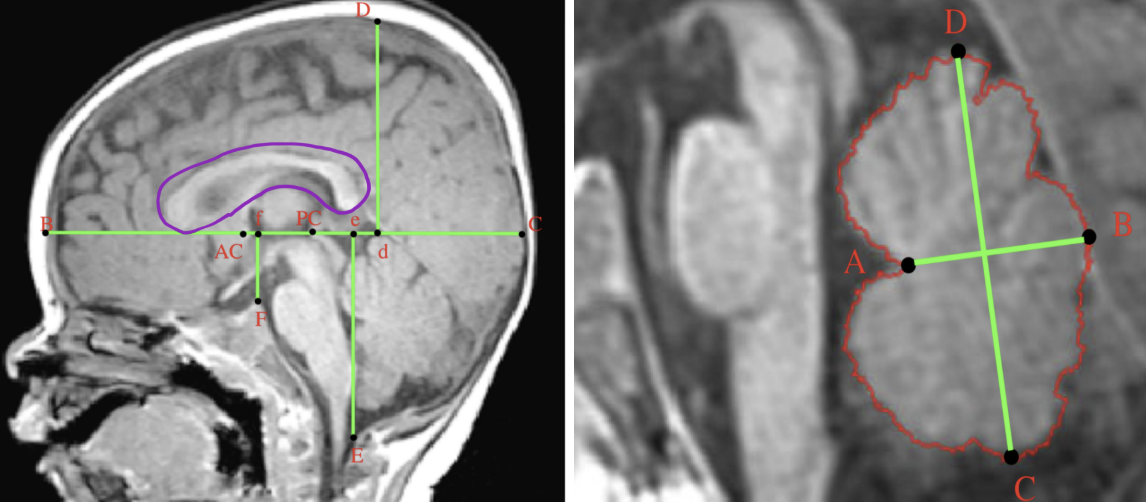

스크린샷 2026-01-26 08.45.34.png 뇌의 구조적 차이를 비교하기 위한 각종 랜드마크 표시

뇌들보의 길이와 각도 차이(보라색으로 표시된 부위)

소뇌벌레의 길이와 폭 비율 차이

(좌) 보라색으로 표시한 ‘뇌들보’라는 부위. 길이 및 각도의 차이를 보인다.

(우) 소뇌벌레의 길이 및 폭 비율에 차이가 있다 (사두증 아기 소뇌벌레 MRI)